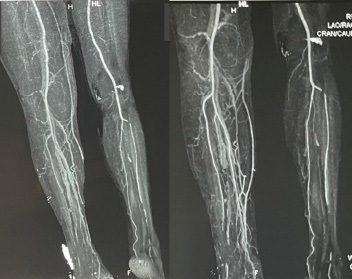

The following day the patient was sent to computed tomography (CT) angiography of the lower extremities. The CT angiogram (Figure 1) showed normal, patent vascular structures without contrast media extravasation. Notable CT abnormalities were swelling of the thigh and multiple loculated fluid collections with air inclusions in the knee region. Additional findings were the presence of free intraabdominal fluid, enlarged cirrhotic liver with portal vein dilatation and splenomegaly. The diagnosis of decompensated liver cirrhosis with severely impaired coagulation was established and the patient was transferred to the Clinic for gastroenterohepatology. Further treatment at our clinic included continuation of transfusions with FFP and packed RBC as needed as well as initiation of standard supportive treatment for decompensated liver cirrhosis with nonselective β-blocker (carvedilol) and diuretic therapy. Assessment regarding the etiology of cirrhosis established alcohol as the causative agent. Despite treatment with blood derivates (7 RBC units and 6 FFP units since initial presentation), a drop-in hemoglobin was noted on several control laboratory analyzes, raising suspicion of ongoing bleeding. Follow-up coagulation profile confirmed persistence of severely impaired clotting ability. After consultation with the traumatologist and transfusiologist, tranexamic acid (tid 0.5 g), cryoprecipatate (10 doses/daily) and enoxaparine (bid 40 mg) were included in the treatment. In the following 5 days there were no signs of ongoing bleeding while laboratory results showed steady improvement in hemoglobin and hematocrit level. The swelling of the right knee and the bluish-black discoloration slowly withdrew. Screening gastroscopy was performed and small straight esophageal varices were detected. After 16 days of hospital treatment the patient was discharged in stable condition. The patient was recommended a complete alcohol abstinence and regular follow up at our outpatient clinic. Up till this moment the patient is in improved and compensated condition in terms of the cirrhosis.

Figure 1a&b: CT angiogram of lower extremities showing patent vasculature of the distal extremitiesBoth images demonstrate integrity of the vasculature of the distal extremities and increased girth of the right thigh and calf due to muscular hematoma.